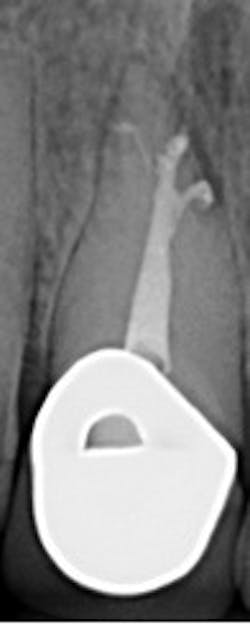

Switching to motorized shaping and carrier-based obturation increases speed and efficiency, which outweighs any addition material cost. The end result is satisfied patients, increased referrals, and greater production. When deciding a file system to streamline the shaping process, the WaveOne system allows for a simplified technique. This system permits deep apical shapes that can accommodate irrigating syringes in the apical third of the canal system. This is the most critical zone of disinfection. Once irrigated, three-dimensional obturation can be quickly and effectively completed with the GuttaCore System. This allows the dentist to deliver heated gutta-percha throughout the canal system, which can result in impressive outcomes. (See photo.)